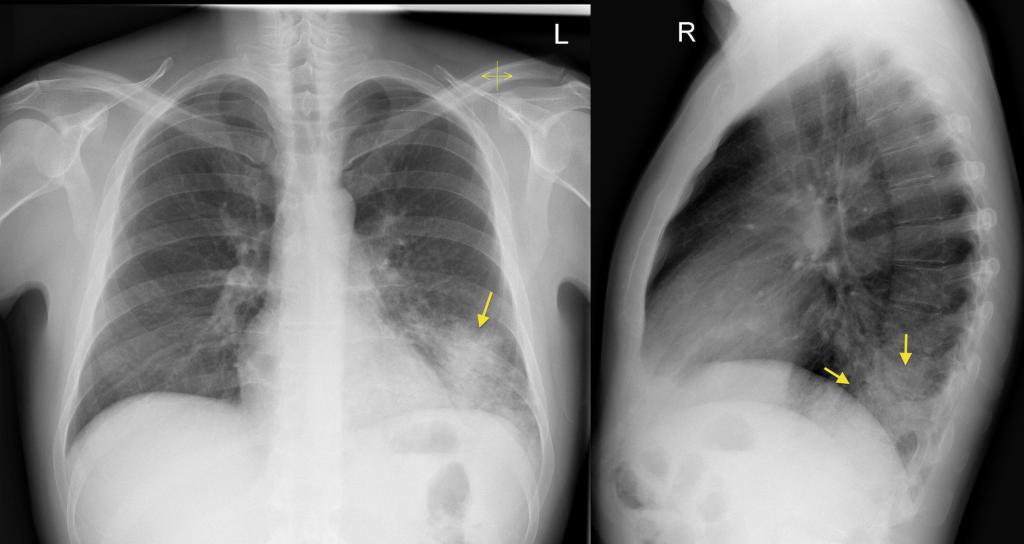

Крупозная пневмония

Как выглядит пневмония на снимке (рентгеновском), если она крупозного вида:

- субтотальные, тотальные затемнения с одного или же двух краев;

- смещение средостения в сторону предельного поражения;

- изменение физического поражения куполов диафрагмы;

- закупорка реберно-диафрагмальных синусов жидкостью;

- полное деформирование легочного рисунка;

- тяжистость корней легких.

Выявить особенности крупозного воспаления возможно на рентгенограмме. Однако при патологии медицинским стандартом диагностики считается рентгенография в двух проекциях (прямая и боковая). Такого рода список процедур совершают для оценки численности пораженных частей легких и исследования состояния средостения.